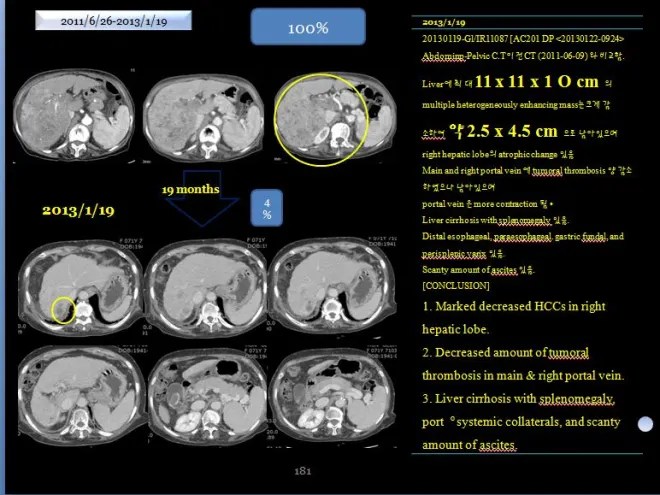

The patient was able to tolerate the course well for nearly two years, with both ascites and pleural effusion resolving, allowing a return to normal daily activities. The CT scan obtained 19 months later showed the findings as above.

As seen in the imaging, the liver had become atrophic; however, the large tumor had almost completely regressed, with only a small residual portion remaining. The medical records at that time documented the following findings.

- A previously noted multiple heterogeneously enhancing mass in the liver, measuring up to 11 × 11 × 10 cm, has markedly decreased in size, with a residual lesion measuring approximately 2.5 × 4.5 cm. Atrophic changes of the right hepatic lobe are also observed.

- Main and right portal vein에 tumoral thrombosis 양 감소하였으나 남아 있으며

- portal vein은 more contraction 됨.

- Liver cirrhosis with splenomegaly 있음.

- Distal esophageal, paraesophageal, gastric fundal, and perisplenic varix 있음.

- Scanty amount of ascites 있음.

- Marked decreased HCCs in right hepatic lobe

- Decreased amount of tumoral thrombosis in main & right portal vein

- Liver cirrhosis with splenomegaly, port。systemic collaterals, and scanty

- amount of ascites

“Comparison of CT scans from June 9, 2011 and January 19, 2013 shows that the previously noted heterogeneously enhancing hepatic tumor, measuring up to 11 × 11 × 10 cm, has markedly decreased in size to approximately 2.5 × 4.5 cm. The right hepatic lobe demonstrates atrophic changes. Tumor-related thrombosis in the main and right portal veins has decreased but remains present, and the portal vein appears further narrowed. Findings of liver cirrhosis and splenomegaly are noted. Varices are observed adjacent to the spleen around the esophagus and stomach, and a small amount of ascites is present.

Within 18 months, the hepatic tumor had decreased to approximately 4% of its original volume. In March 2014, I was invited to present at the Korea–China–Japan Integrative Medicine Conference, and in preparation for this presentation, I recommended that the patient undergo a follow-up CT scan after about one year.